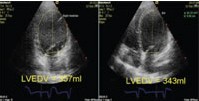

图2A CRT前的左室舒张末容积(LVEDV)

图2B CRT后LVEDV减小